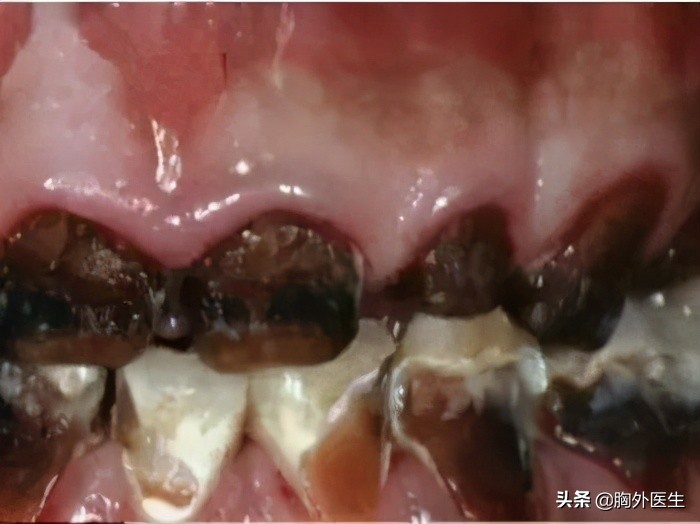

4、龋齿

碳酸饮料中的碳酸会腐蚀牙齿,如果不注意口腔卫生,容易出现蛀牙。